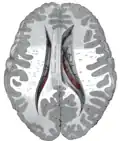

Caudate nuclei along with other subcortical structures, in glass brain -